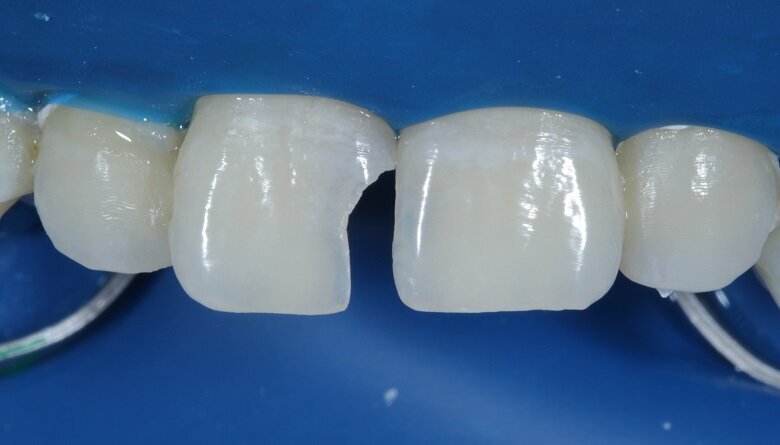

Fig 12: Palatal Shell (Free Hand)

The tooth surface was then cured for 20 seconds. A free hand palatal shell was built using A2 enamel shade which gave the restoration a basic structure and is the first step of layering (Fig 12). Tooth no. 21 was built up palatally using A2 dentin and body shade.